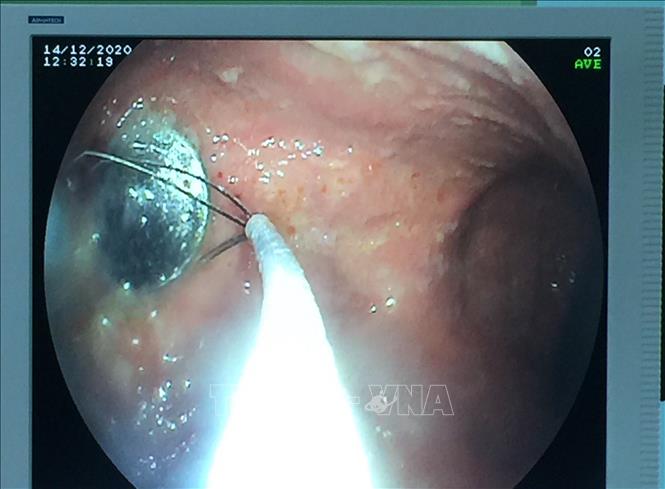

Trong ảnh: Đồng xu được nội soi gắp ra khỏi cơ thể bé gái 4 tuổi do nuốt phải trong lúc chơi đùa. Ảnh: TTXVN phát

Chiều 15/12/2020, Bệnh viện Hoàn Mỹ Đà Nẵng vừa nội soi can thiệp cấp cứu thành công, gắp được dị vật là một đồng xu nằm ở dạ dày của bệnh nhân nhi 4 tuổi do nuốt phải trong lúc chơi đùa. Hiện sức khỏe bệnh nhi đã hồi phục bình thường. Ảnh: TTXVN phát